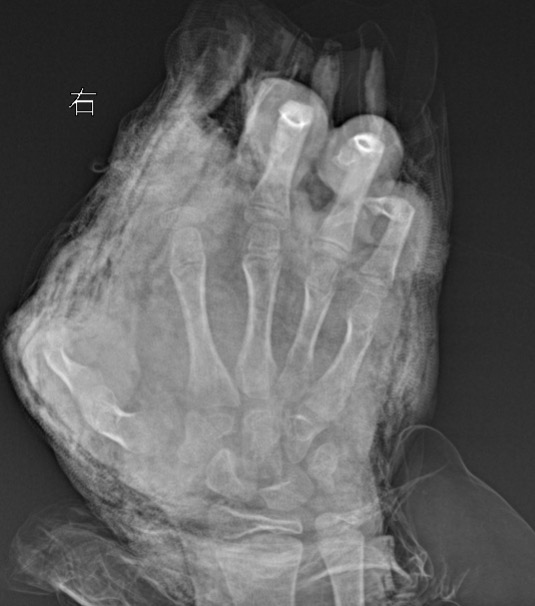

“孩子来院时,伤情触目惊心。”徐剑告诉记者,双手血肉模糊,脸上和胸前均有炸裂伤。右手伤得最重,食指离断,拇指前段皮肉被炸飞,仅剩半截骨头,中指末节缺损,虎口处的伤口还嵌入了小石子。

为防止伤口感染和出现其他继发性组织坏死,当晚11点,医生立即为其进行急诊清创手术。虽然孩子拇指远节毁损,但拇指近节仍有血供存在。手术医生徐剑和欧阳富成,竭尽全力帮孩子保留右手拇指近节功能及更多的手部功能。

术中,医生们在剥离拇指失活及坏死组织的同时,小心翼翼保护尚存的细小血管。随后对中指缺损部位及环指和小指指腹进行清创修复……直至2月6日凌晨3点手术才结束。

据徐剑介绍,由于孩子的手掌和手指炸伤非常严重,离断的食指因为血管和肌腱撕裂严重无法再植。目前还要继续观伤情,择期进行二次清创及修复手术。